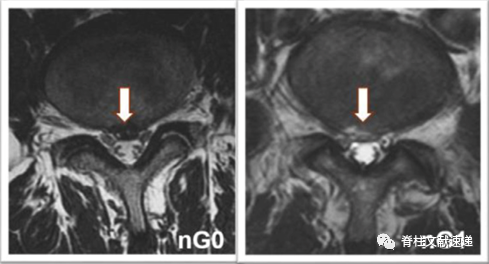

0级:椎间盘与神经根(nG0)或硬膜囊(dG0)之间存在空间;

1级:椎间盘与神经根接触但未受压(nG1),或硬膜囊受压<椎管的1/3(dG1);

2级:神经根受压移位(nG2),或硬膜囊受压>1/3而<1/2(dG2)。

3级:神经根受压且和椎间盘组织不易区分(nG3),或硬膜囊受压>1/2(dG3)。